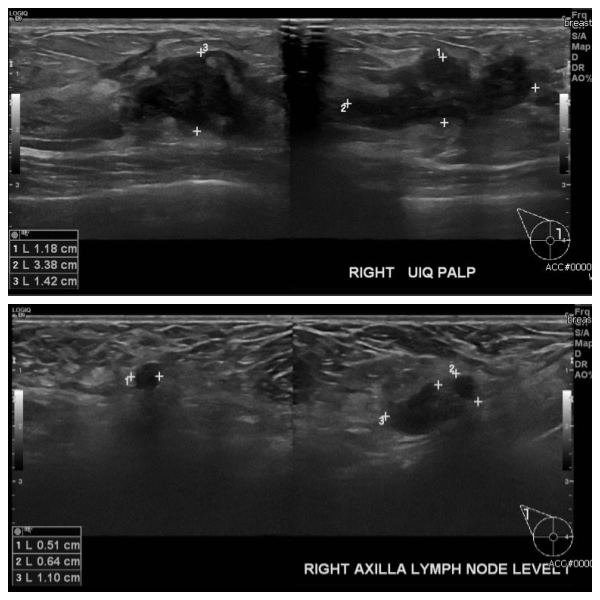

우측 만져지는 멍우리로 내원하신 30대 여성분으로 우측 만져지는 혹 중앙핵생검 시행하여 침윤성 암 진단 되었고, 우측 겨드랑이 림프절비대 세포검사 시행하여 전이암 진단 되었습니다.